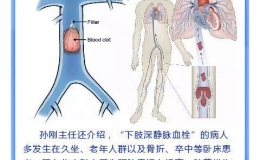

“网”住夺命“鱼” 畅通生命“渠”——记东方总院普外科“下腔静脉滤器植入术”

【综合新闻】 2018-12-21 15:52:00 196 次 -